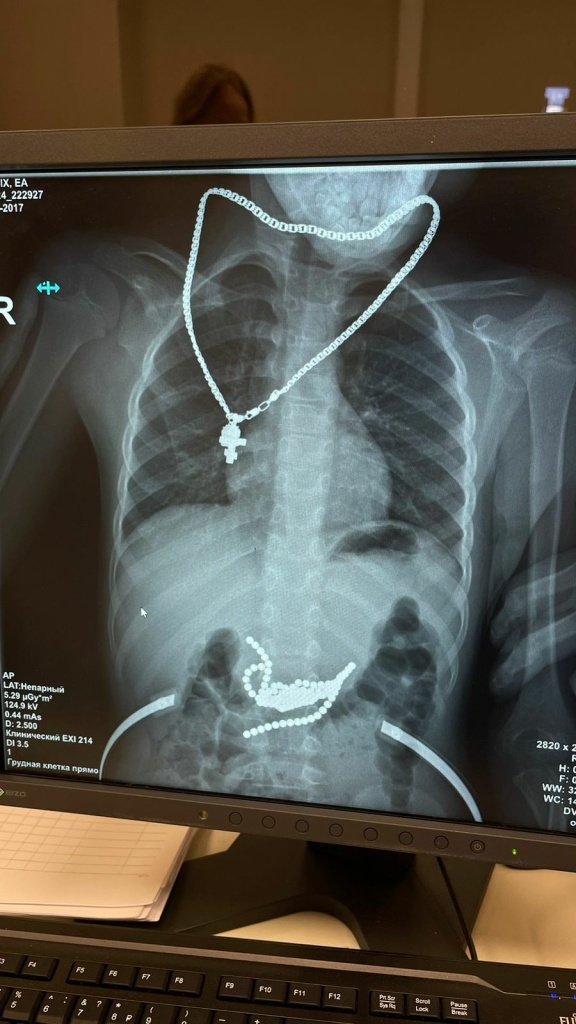

Родители быстро обратились в приемное отделение ГБУ РО «ОДКБ», и на обзорном R-cнимке магнитные шарики были отлично видны. Эндоскопическая попытка извлечь их оказалась безуспешной – из-за их миграции в подслизистый и мышечный слой желудка. В итоге – полостная операция, очень сложная. Её выполнили заведующий хирургическим отделением №1 Глеб Новошинов, хирурги Антон Штарев и Иван Попов, анестезиологическое пособие проводила анестезиолог Юлия Переймак.

На фото: рентгенограмма пациента, где в проекции желудка видно «ожерелье» из магнитов.